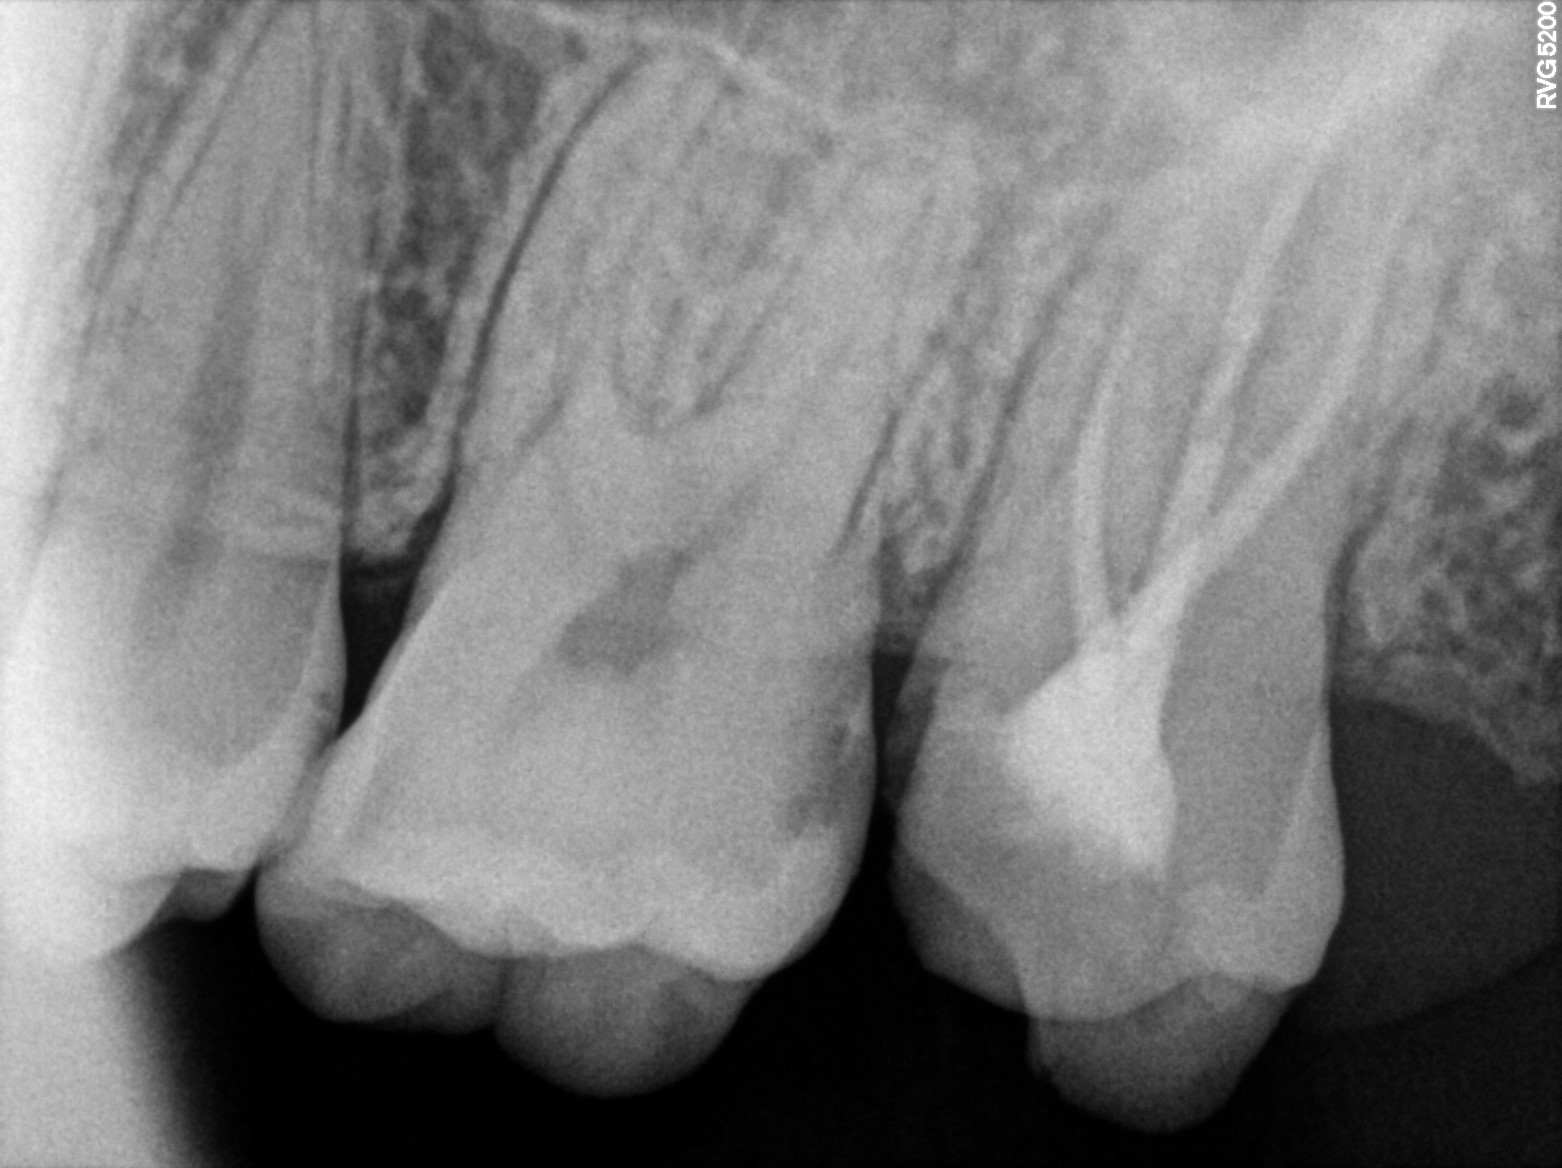

Dental Radiographs FHIR: DocumentReference · LOINC 24641-7

xray_1744445313.jpg

24641-7

| Dental filling | 180534004 | D2940 Protective restoration (GIC) | ##16 | 2025-04-30 | completed | type ix with 16,distal smooth surface lesion | |

| Crown of tooth | 424311000 | D2750 Crown, porcelain fused to high noble metal | ##17 | 2025-04-30 | completed | cementaion with 17,endo crown metal | |

| Crown of tooth | 424311000 | D2750 Crown, porcelain fused to high noble metal | ##27 | 2025-04-26 | completed | cutting done with 27 | |

| Dental caries | — | 80967001 | resolved | 2025-04-30 | type ix with 16,distal smooth surface lesion | |

| Dental caries | — | 80967001 | resolved | 2025-04-26 | cutting done with 27 | |